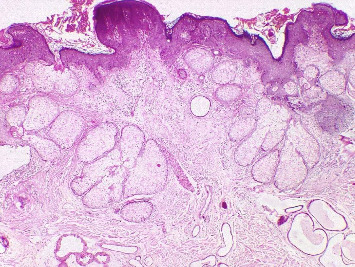

Histopathological Features of Nevus Sebaceous and Superimposed Skin Tumors.

Introduction: Nevus sebaceous (NS) is a rare congenital hamartoma that may cause some concerns for parents. Benign skin tumors can develop in NS, although malignant transformations have occasionally been documented. This study aimed to investigate the histopathological characteristics of NS lesions in relation to sex, age, location, type, and any associated superimposed tumors. Methods: This retrospective cross-sectional study was conducted on the histopathologic reports of 60 patients with NS who were referred to our center between 2010 and 2022. Information, including sex, age, location of the lesion, and histopathological features of the NS lesion, was recorded. Results: The mean age of the patients was 24.52 ± 12.19 years, and 65.0% of the patients (39 cases) were men. Most of the lesions were observed on the scalp and face. Benign and malignant neoplasms were observed in 5% and 10% of patients, respectively. All the cases of malignant tumors (six cases) were identified as basal cell carcinoma, and three cases were benign tumors of syringocystadenoma papilliferum. Demodex infestation and apocrine gland dilatation were observed in 56.7% and 23.3% of patients, respectively. Benign neoplasms were significantly more frequent in women (p=0.039). In addition, malignant neoplasms were significantly more prevalent among patients aged ≥ 25 years (p=0.001). The frequencies of acanthosis and focal parakeratosis were higher in the scalp, and sebaceous hyperplasia was more common in the face (p < 0.05). Conclusion: Our study revealed that malignant tumors were more common than benign lesions in patients with NS. Benign neoplasms were more frequent in women. Malignant neoplasms were detected in patients aged more than 25 years.

Abstract Image